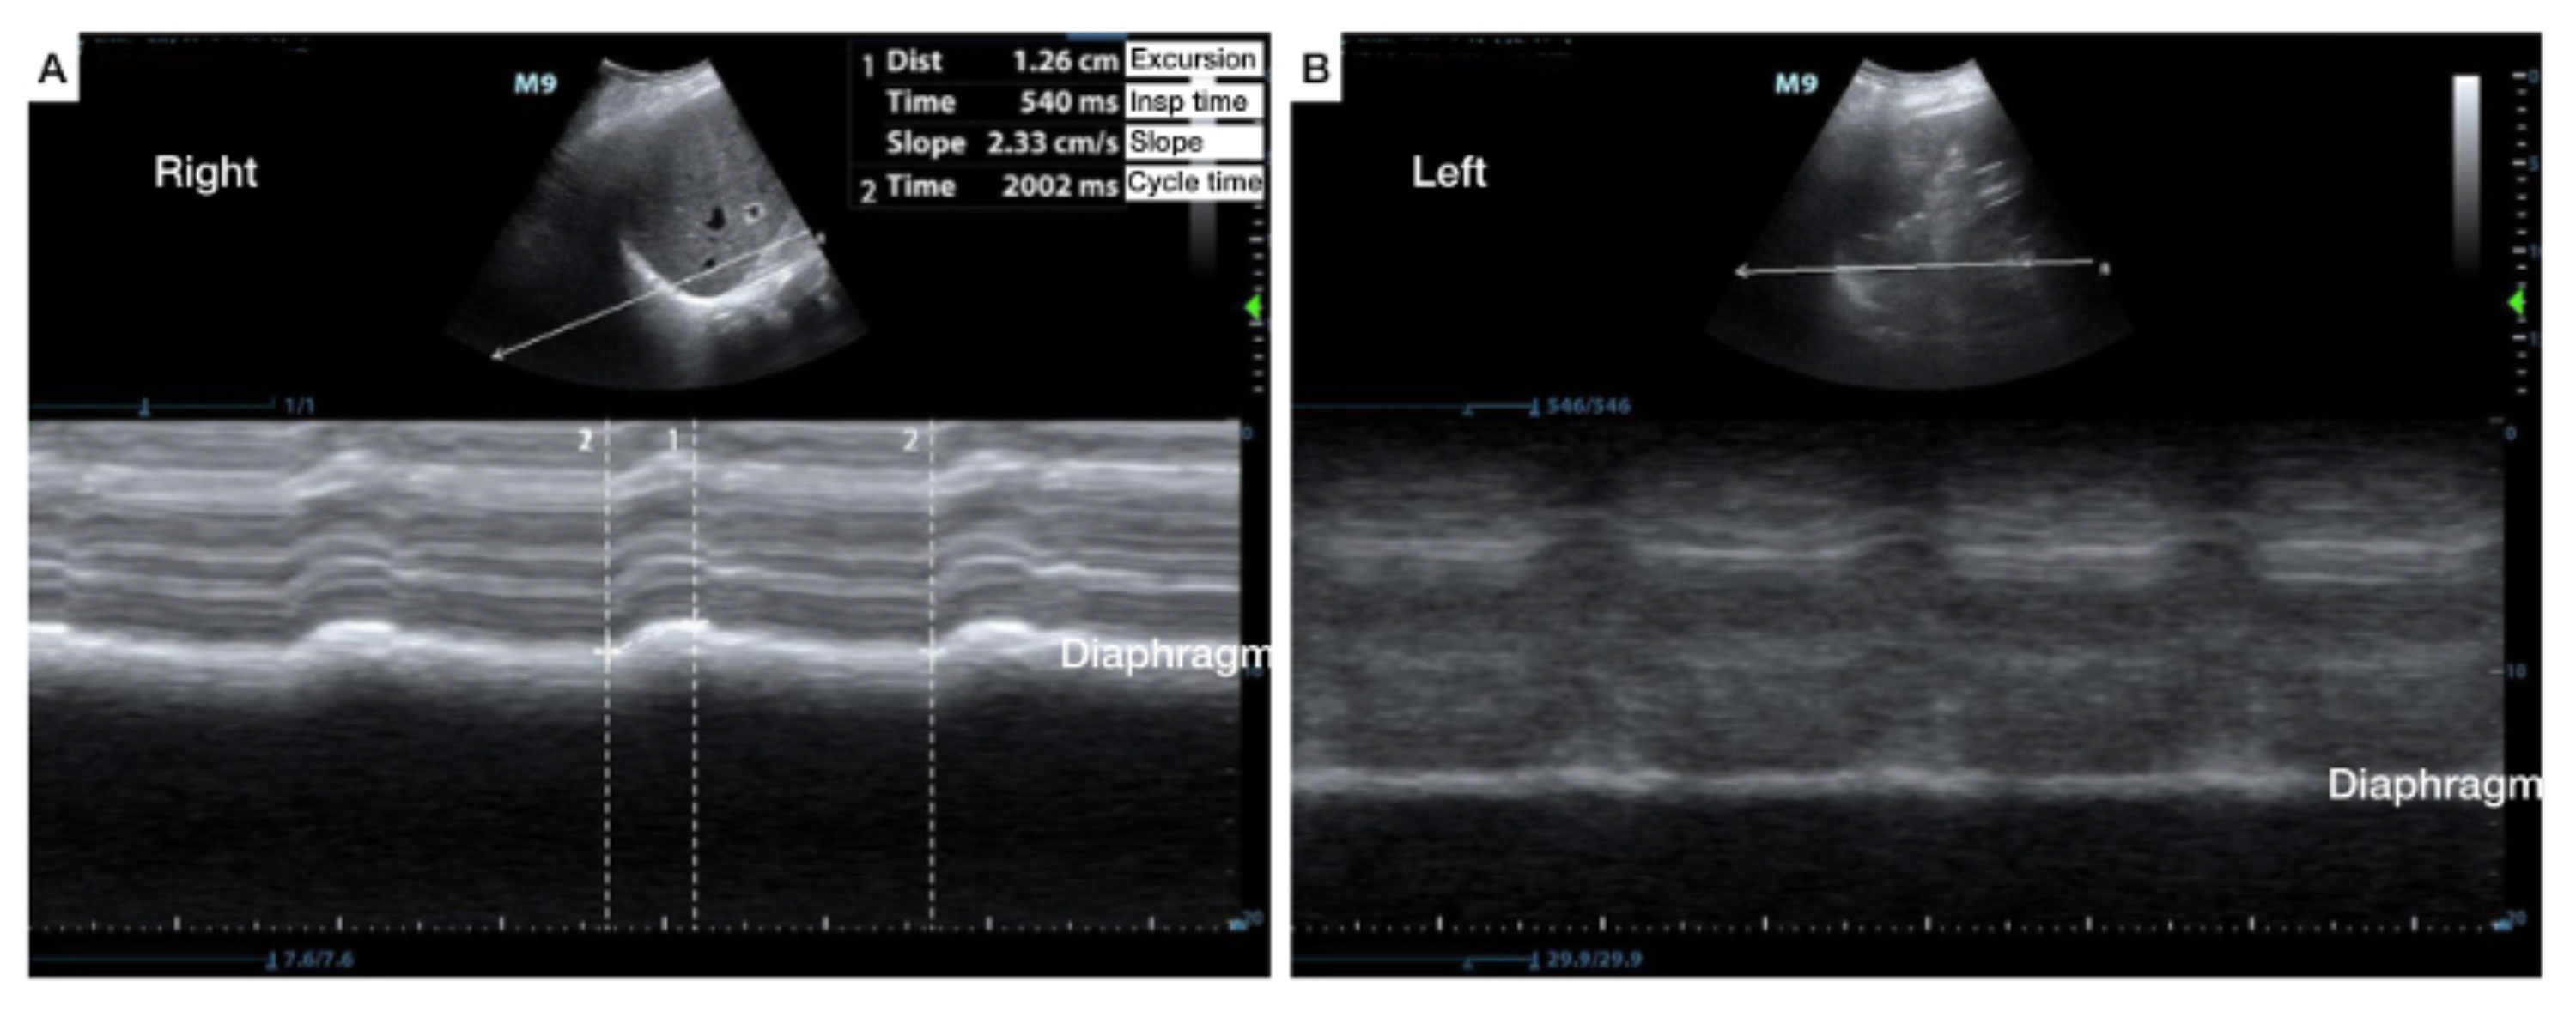

The measurement of diaphragmatic thickness and excursion. (A) A 1015 Diaphragmatic Excursion Evaluation We found an outstanding value for. Several monitoring tools can be used to assess diaphragm activity and function during mechanical ventilation, including pressure. This study looked at the role of diaphragm excursion (de) and thickening fraction in predicting successful extubation from mechanical ventilation. Various authors have described ultrasound techniques to assess diaphragmatic excursion and diaphragm thickening in the zone of.. Diaphragmatic Excursion Evaluation.